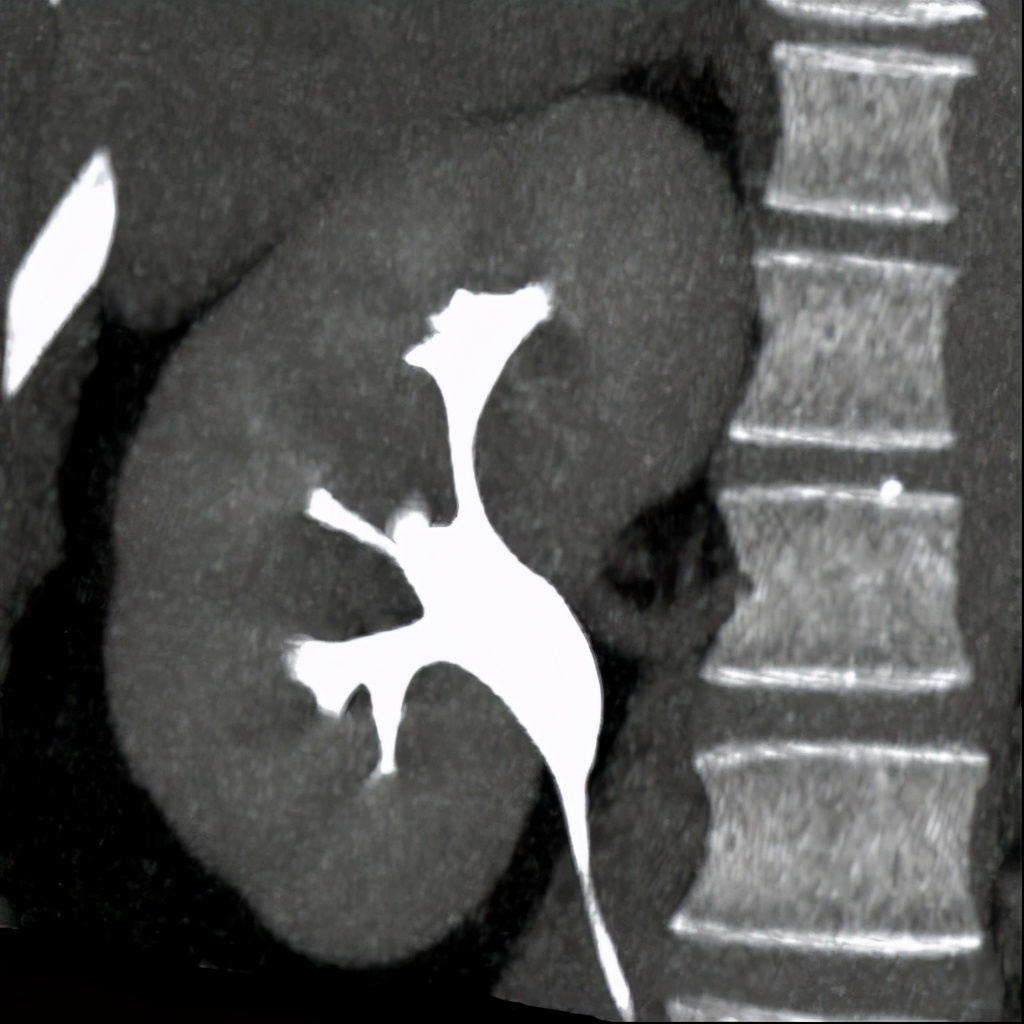

上图所示:体检B超示(右)肾积水,行CT尿路造影检查。左图示平扫后重建示(右)肾囊肿向肾盂内突出。右图示,静脉注入造影剂、经过一定时间延迟后,(右侧)输尿管起始处造影剂充盈良好,肾盂内囊肿内未见造影剂填充。 (二)肾外肾盂: 正常人肾盂大多位于肾窦内,成为肾内肾盂;少数位于肾窦外,成为肾外肾盂。肾外肾盂属于正常肾盂的一种情况,可见于任何年龄。

上图所示:右侧甚肾盂增宽,并延伸至右肾盂外侧,其远端无梗阻因素,考虑肾外肾盂。